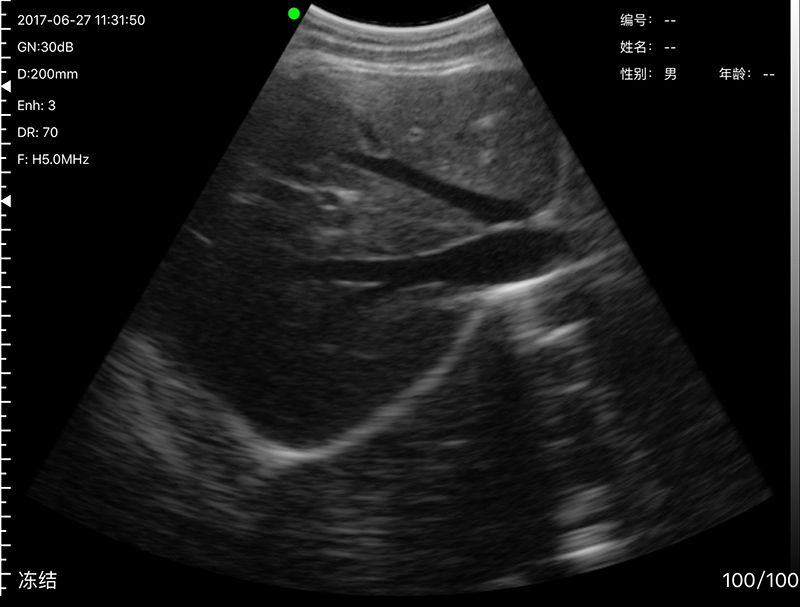

• 穿刺辅助功能:平面内穿刺引导线功能,平面外穿

刺引导与血管自动测量功能,针尖显影增强功能